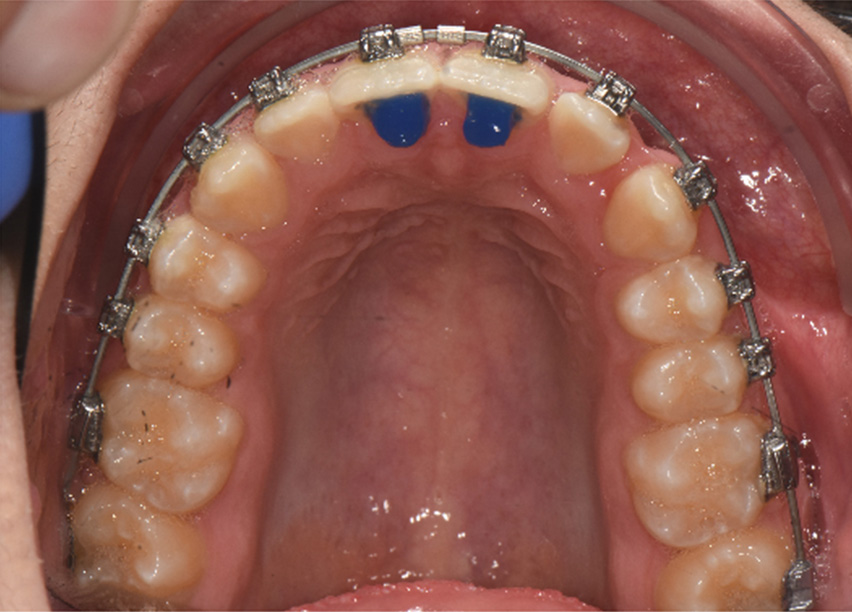

Variable torque Damon Ultima brackets were chosen for this case. Neutral torque on U2-2 & L1 & L3, proclined torque on U3, retroclined torque on L2 due to crowding and objective of torque control. All permanent teeth were bonded, the bite was disarticulated. The U2-2 brackets were positioned vertically higher to improve the smile arc.

Initial wires U 0.014 CuNiTi Ultima and L 0.013 CuNiTi Ultima were ligated without the second molars. On U2’s buttons were bonded with indirect ligation to half bracket width coil spring. We bonded anterior bite turbos on U1’s.

Observations: At the end of phase 1, most of the rotations had been corrected and arch development was progressing well. The crowding had been resolved and spaces were visible due to arch development with the first rectangular wire. Additionally, primary torque control was observed. The time frame of these changes was six months.